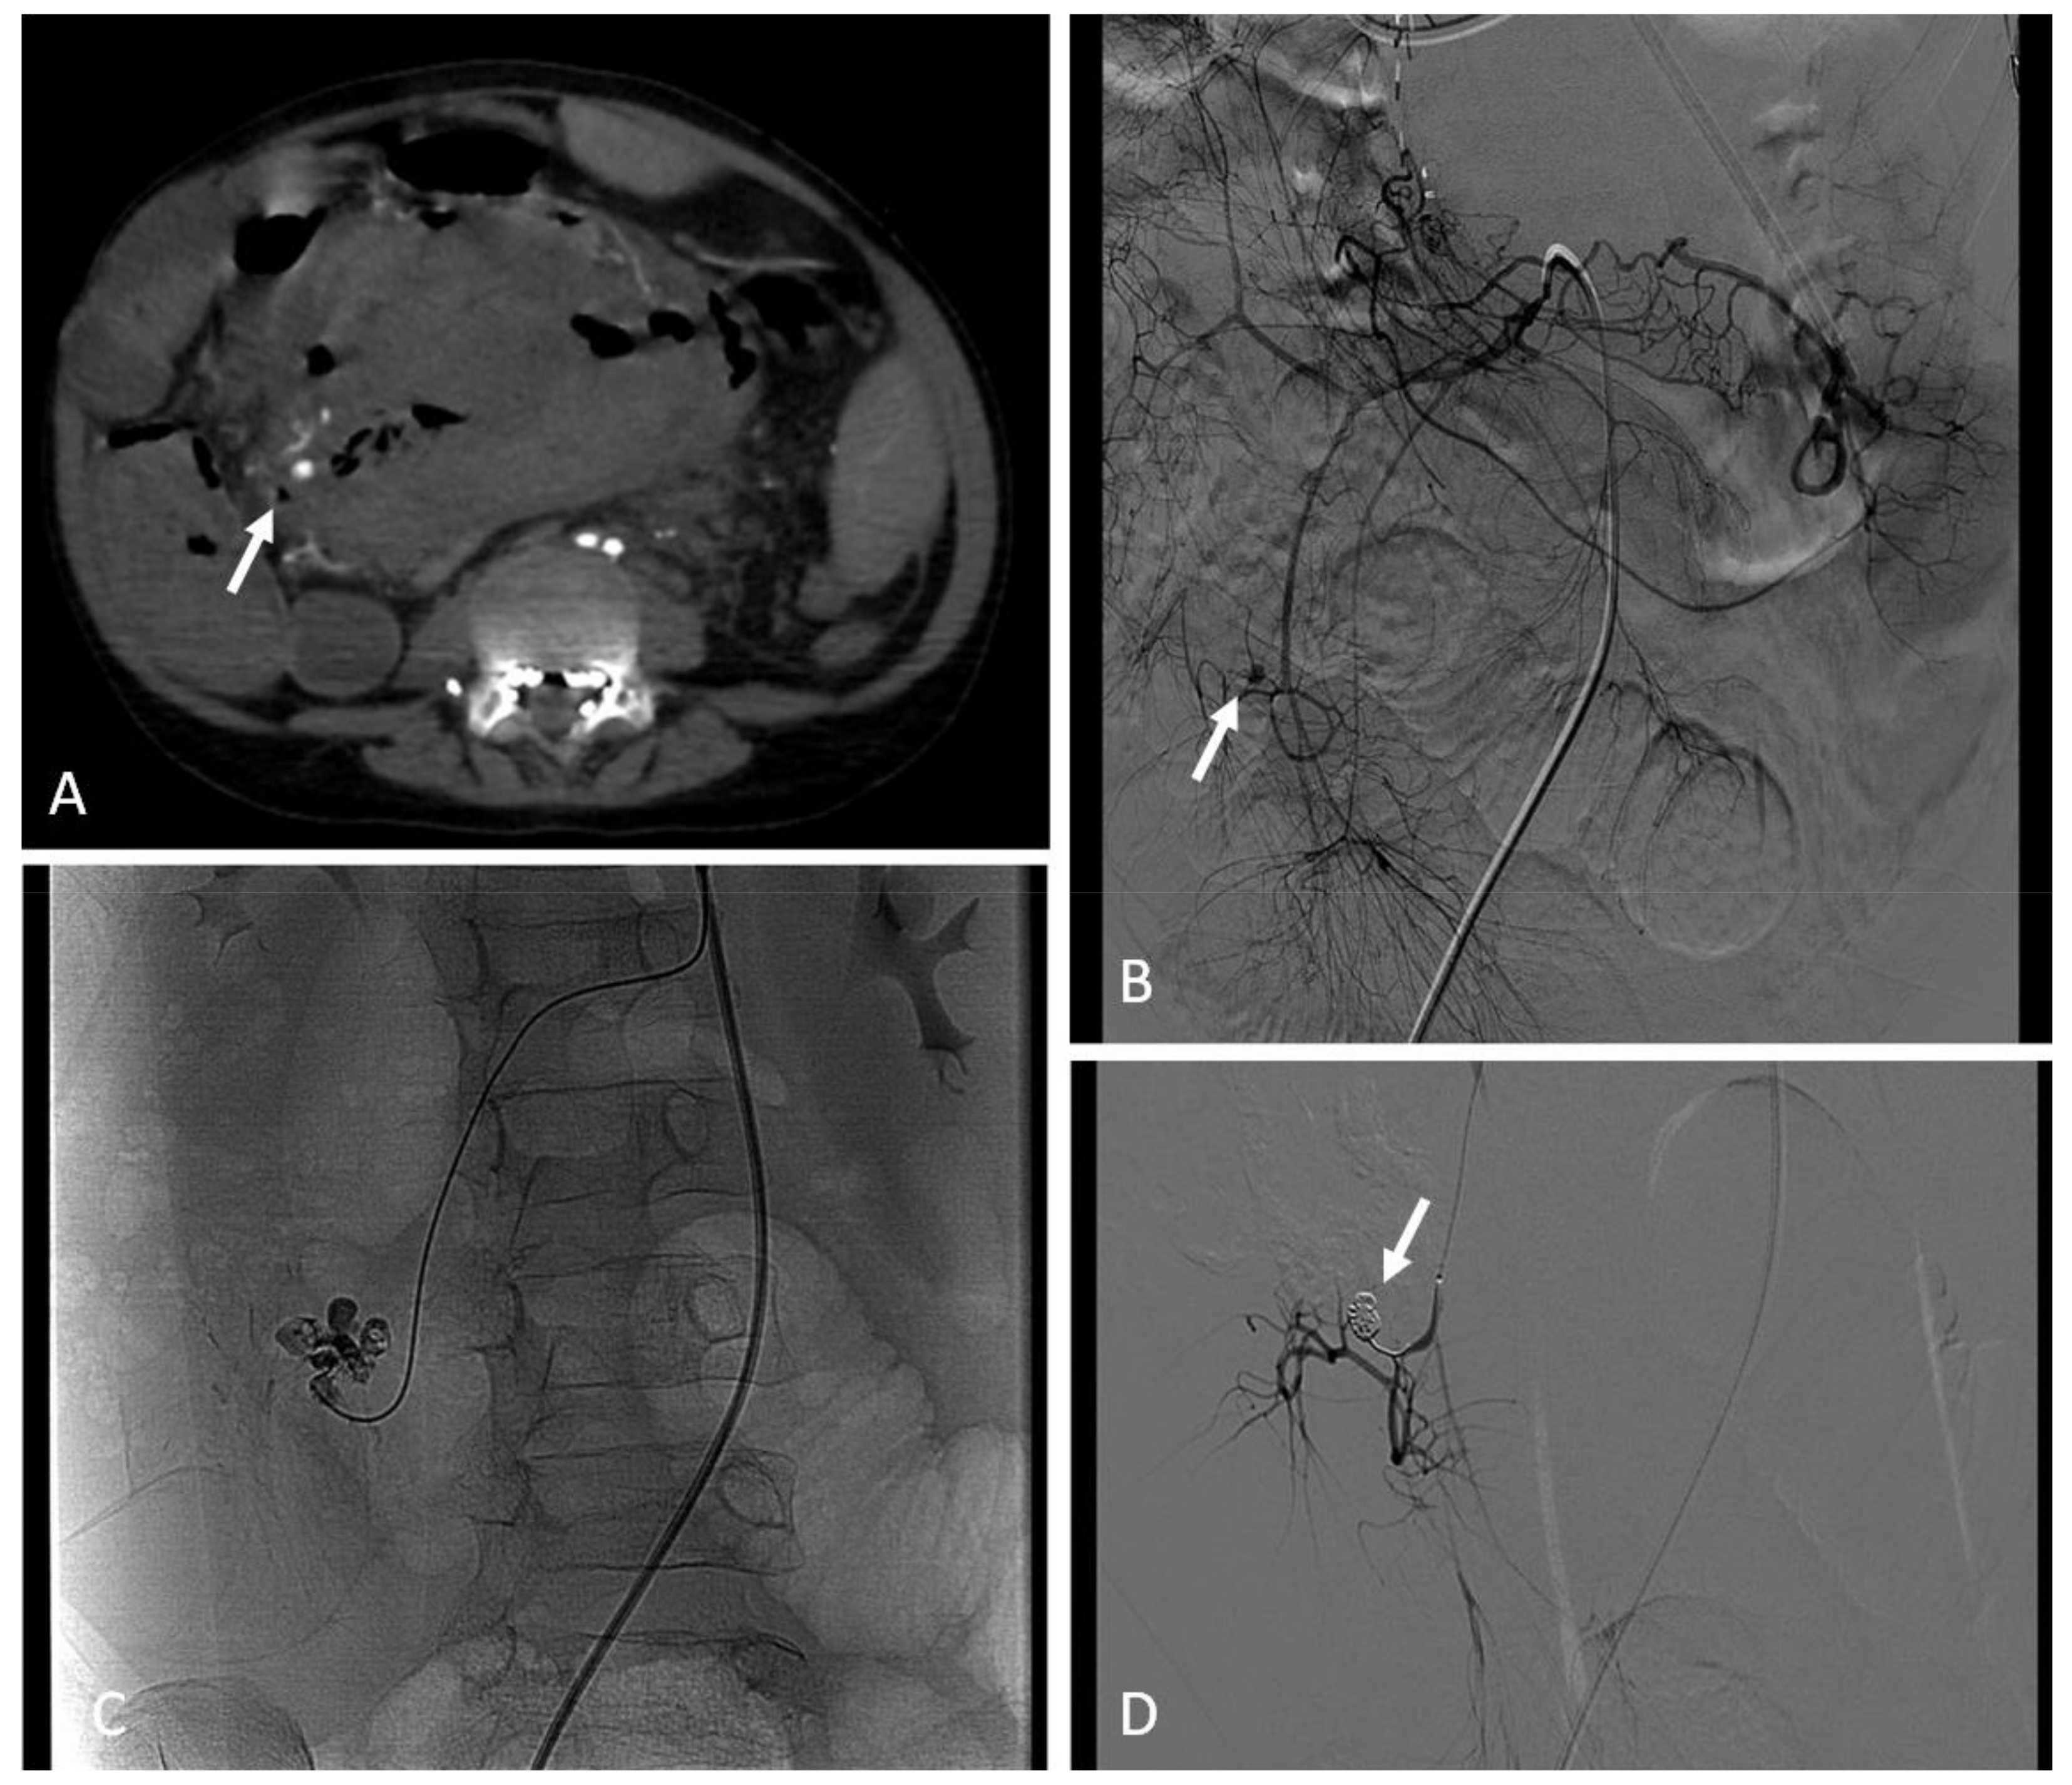

8.3.3. Renal Angiomyolipoma